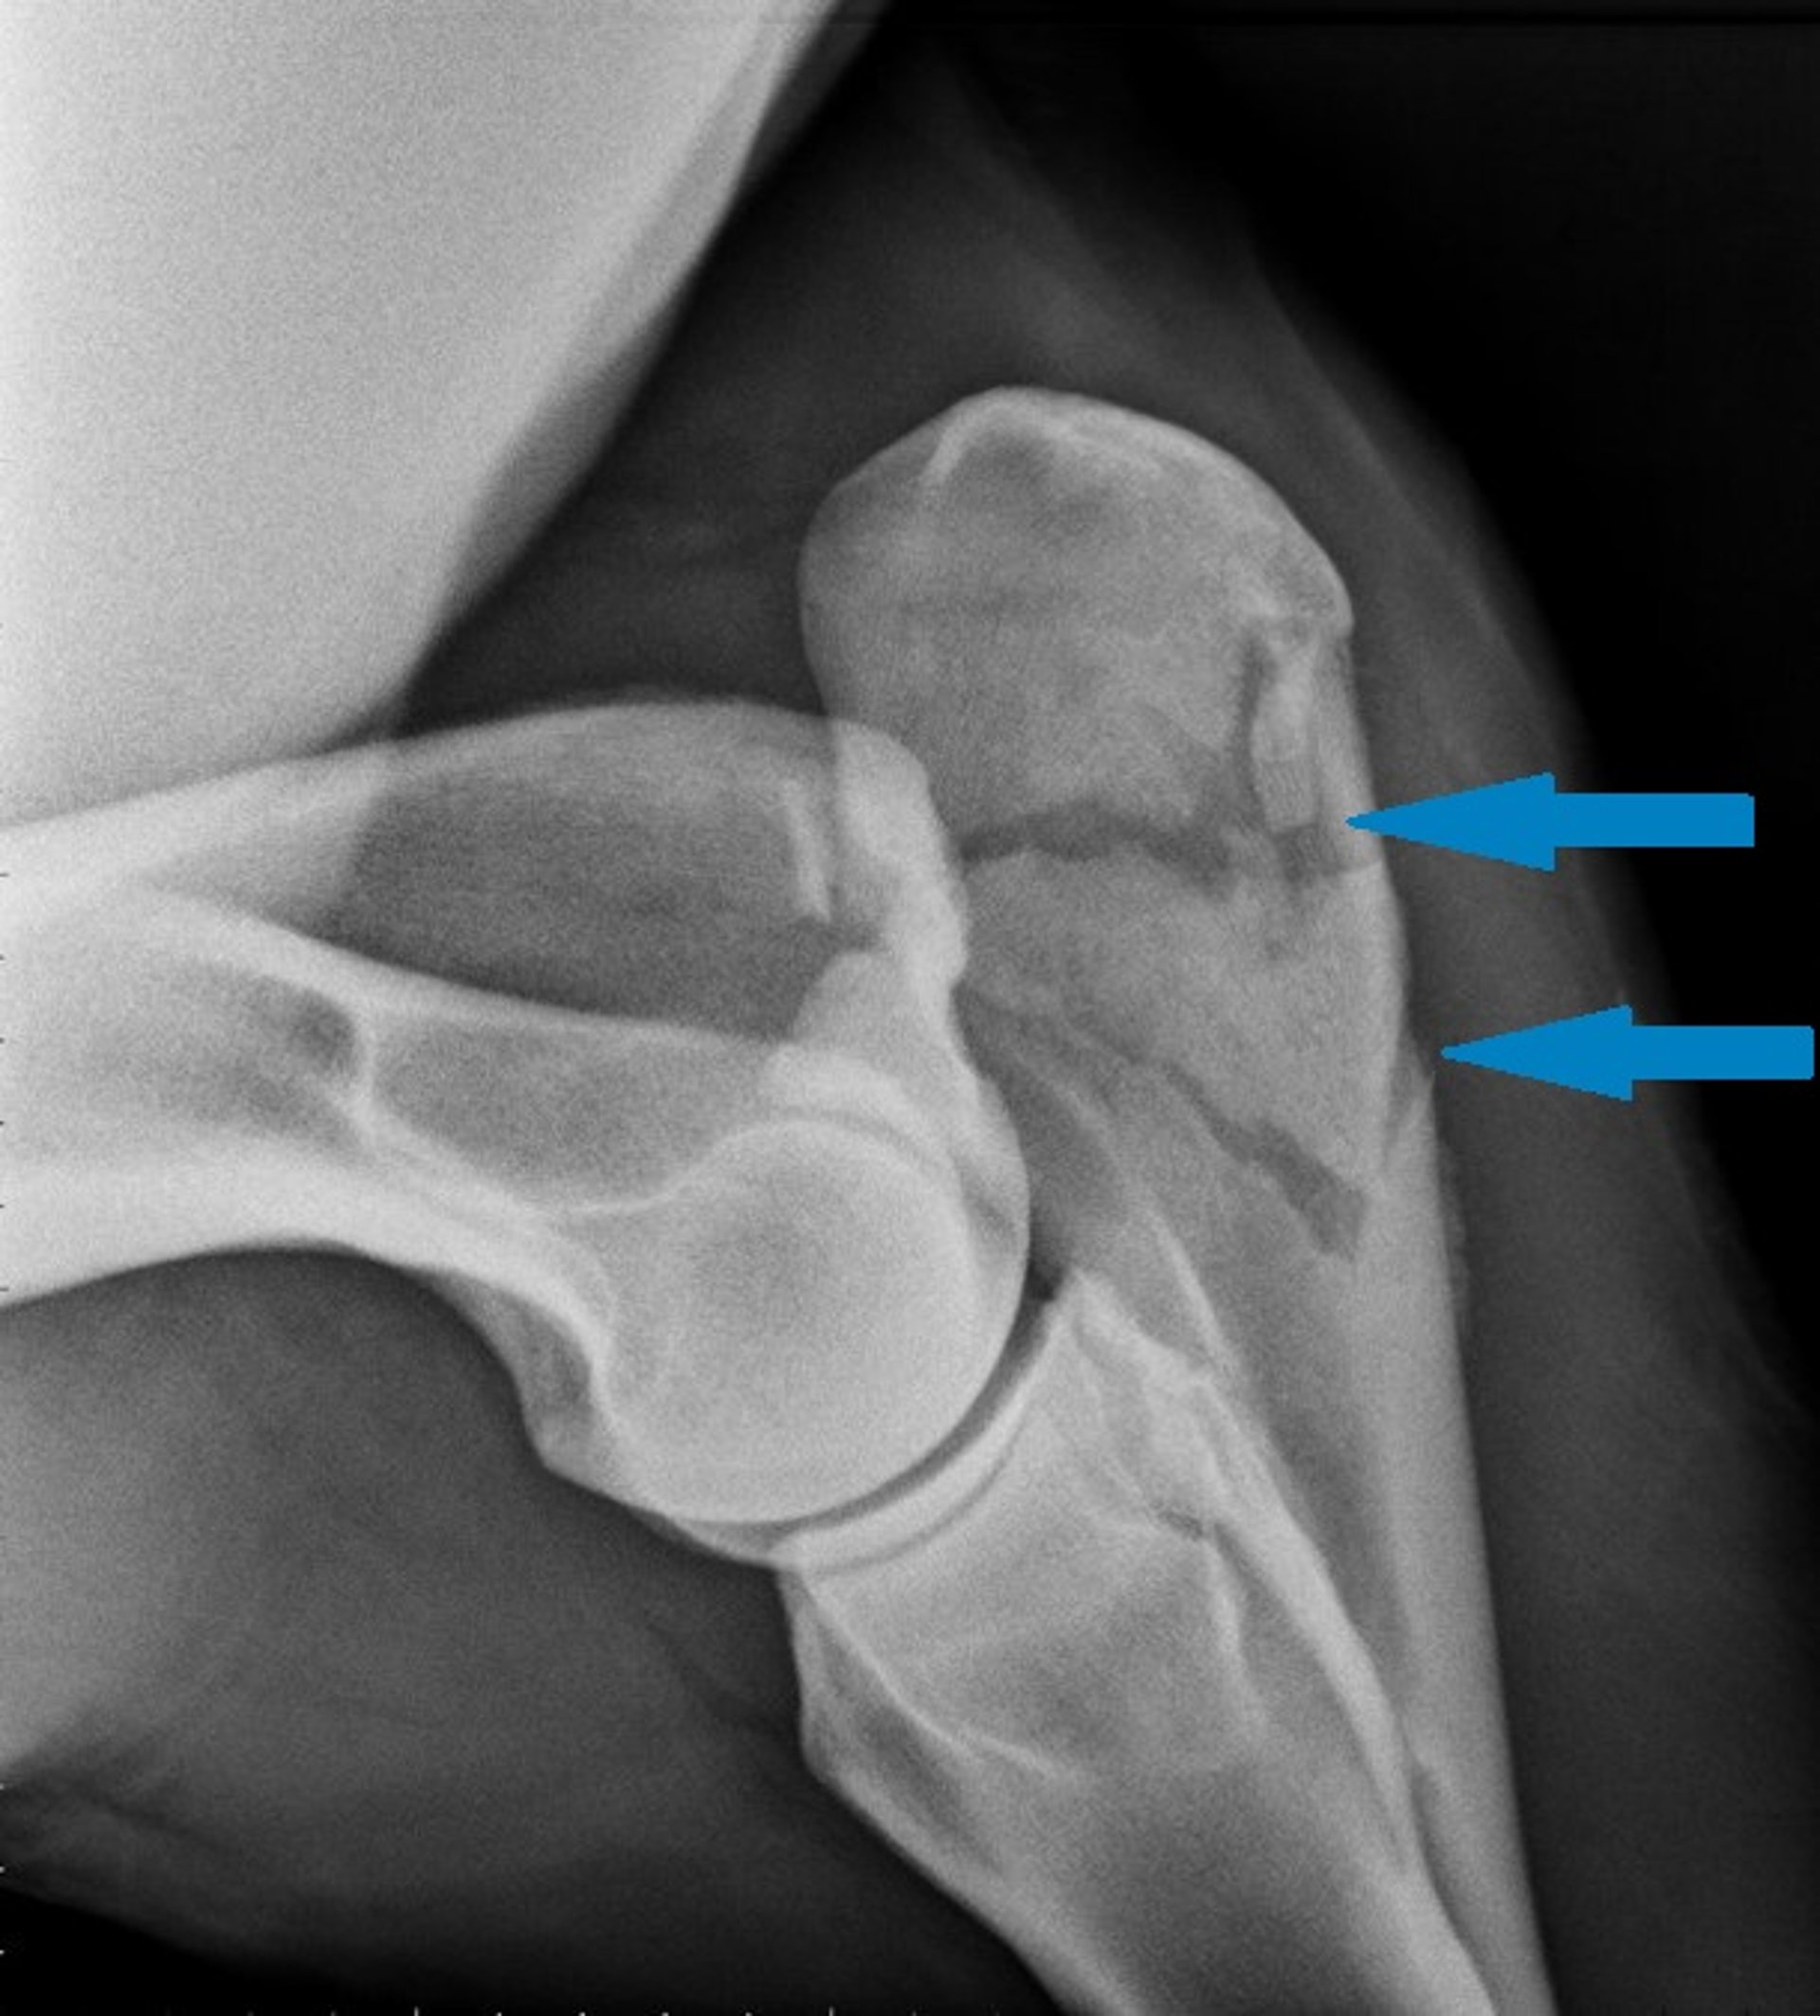

Ulnar fracture, radiograph, horse

Radiographic image showing a comminuted ulnar fracture (arrows) in a horse.

Courtesy of Dr. Tracy A. Turner.